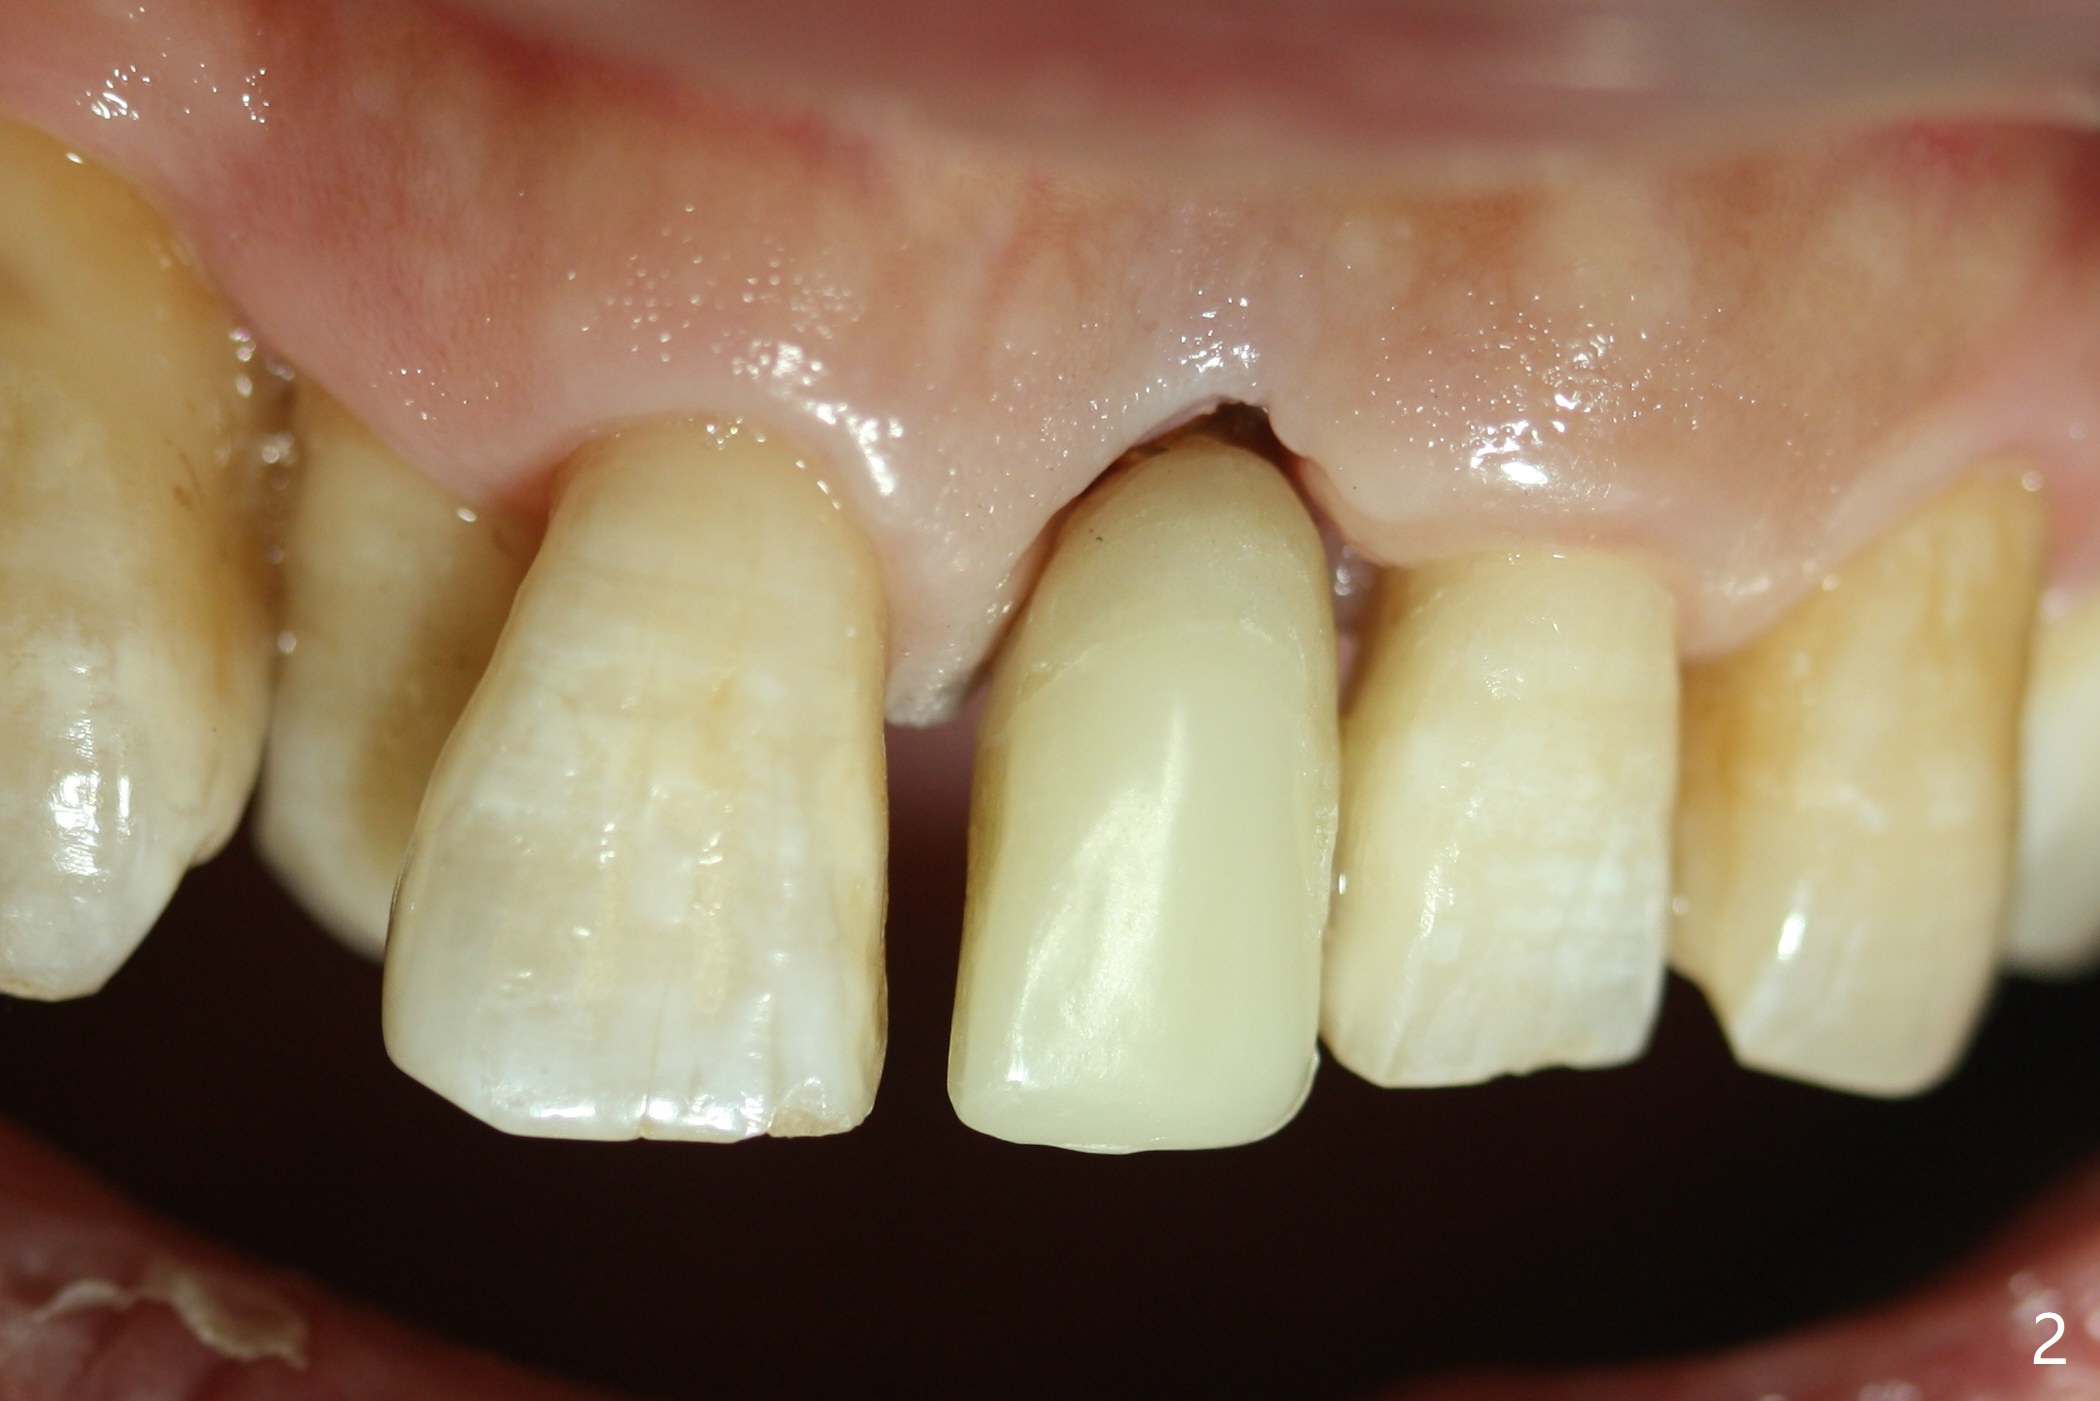

Nearly 7 months postop, the immediate provisional at UL1 is removed; with the mesial reduction of UL2 from 7 to 6 mm (Fig.1), an angled abutment is to be changed (4.5x15 degree, 2 mm cuff). A new provisional (Fig.2,3) co-incides with the facial midline. Brackets will be placed between UR4 to UL3 except UL2 (symptomatic once with chronic periodontitis) with initial proximal reduction between UR1-4 in preparation to correct cross bite of UR2. Twelve days later, the patient returns for UR5-UL3 bracketing after UR1-4 initial proximal reduction with 14 niti wire (Fig.4-6). UR1 moves mesial 20 days post open coil spring (Fig.7 arrow), while UL1 debracketes after permanent re-cementation of the temporary crown last visit (*, no re-bracketing, since it appears not essential). Before placement of 20 ss wire, diastemata are created by proximal reduction (Fig.8 *). In fact UR1 moves mesial, while UR3 does not move distal with the open coil. With placement of UR6 (implant) molar band, UR3 is distalized effectively. With sling shot, UR2 is almost labialized in one appointment (Fig.9). After consolidation of the diastemata between UR1-6 with power chains following UR2 cross bite correction (Fig.10), the restoration space for UL1 seems to be too large (Fig.11). Next visit, check the midlines, take 1-2 PAs for #7-9 and determine whether a straight abutment should be changed back and whether composite should be placed UR1 mesial to reduce the space. One week later, composite is added to the mesial surface of the tooth #8 to increase its width, while the provisional at #9 is relined to improve the interdental papilla (Fig.12). Minimal bone loss at UR2 is observed 8 months post banding (Fig.13), while the socket at UL1 seems to have healed except the most coronal 1 year 3 months postop (Fig.14 *). The margin of the abutment should be uneven, more coronal proximal than buccopalatal (Fig.15). The final crown has an open margin, partially due to less ideal trajectory (Fig.16 (black line: ideal trajectory, nearly 1 year 4 months postop)). Guided surgery could solve the problem. Sticky bone may restore the buccal plate defect. Die shows that the implant is palatally placed (Fig.17). CT will be taken to determine whether the implant perforates the palatal plate.